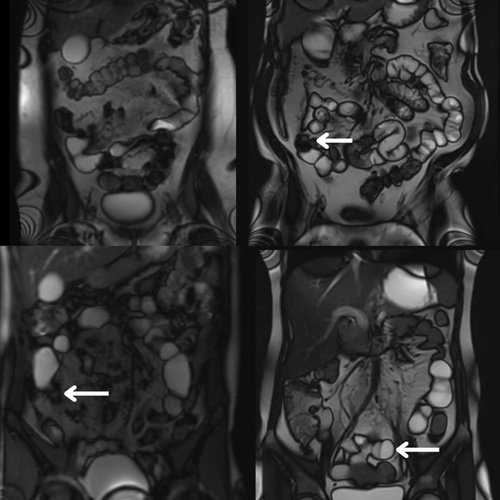

Imaging fibrostenotic Crohn’s disease

Fibrostenotic Crohn’s disease is complex, with strictures that are difficult to assess and treat. Motilent is creating imaging tools that capture treatment response and support better trials and patient outcomes.